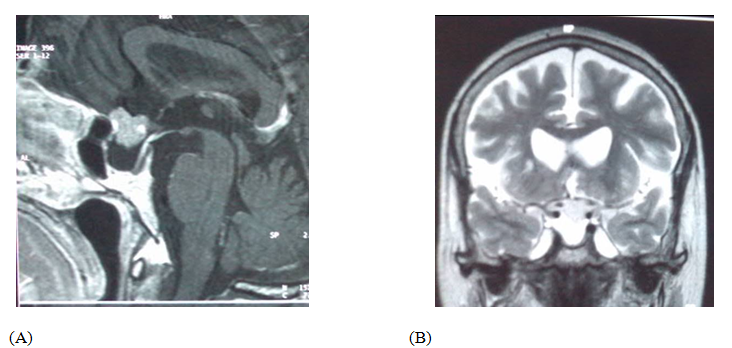

Compressive pneumocephalus is a rare condition, most often secondary to head trauma or surgery. We report post-operativecompressive pneumocephalus in a patient who underwent primary surgery for anterior clinoidmeningioma complicated by CSF leakage treated by lumbar spinal drainage. CT scanclearly demonstrates a compressive pneumocephaluswith the sign of the Mount Fuji. The patient was treated with definite bed rest and plenty of fluid replacement with good outcome. Compressive pneumocephalus is a serious, infrequent complication anda possible cause of postoperative worsening.Medical treatment combining highly inspired oxygen therapy and rehydration are sufficient to correct the condition.

CT scan showed a huge compressive bifrontalpneumocephaluswith the Mount Fuji sign (Figure 2). The decision made is to treat the patient using a rehydration regimen with daily control by an ionogram, bed rest, plenty of fluid replacement and clamping the spinal drainage. The outcome was favorable with a return to a clear consciousness without rhinorrhea or neurological deficit, also with a good control of brain CT (Figure 3).